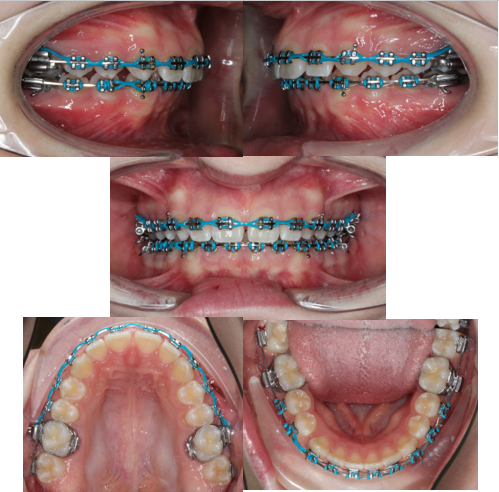

Neextrakční terapie: převislý skus

Začátek: tzv. převislý skus (stav na začátku)

Průběh léčby plným fixním aparátem

Konec po sejmutí: po sejmutí zámků z horních i dolních zubů oblouky harmonicky artikulují k sobě (zuby se dokousnou k sobě)